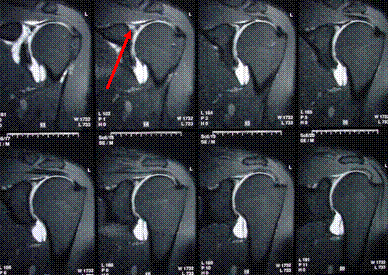

“SLAP” lesion